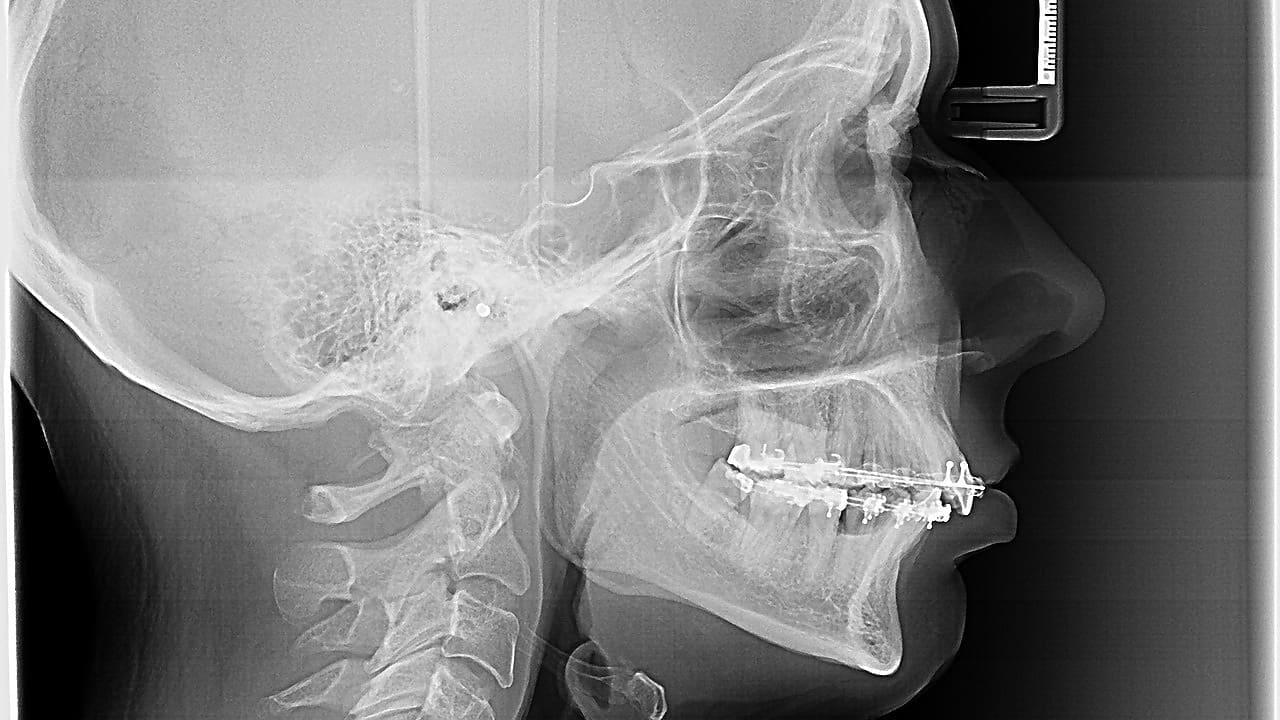

ACDF is a surgery that removes a bad disc and fuses the vertebrae together. Discectomy means taking out a damaged disc. Fusion means joining the vertebrae with a bone graft and sometimes plates or screws. It aims to ease pressure on nerves and improve movement.

To stabilize the spine and promote fusion, we use an anterior cervical plate. This plate is secured with screws that are inserted into the adjacent vertebrae. The plating system provides immediate stability and supports the fusion process.

| Anterior Cervical Plating | Using a plate and screws to stabilize the spine | Immediate stability, promotes fusion |

| Bone Grafting | Inserting a bone graft to facilitate fusion | Promotes bone growth, enhances stability |